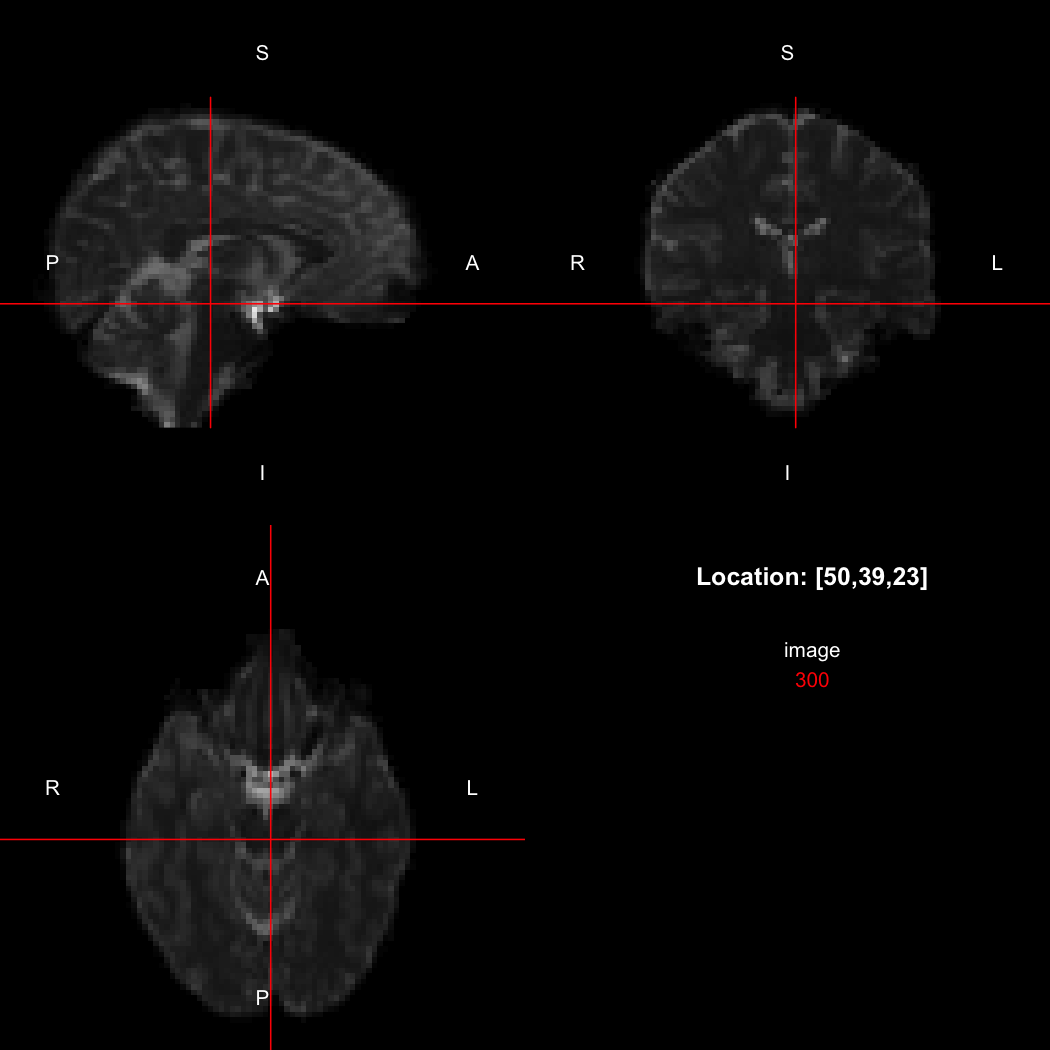

The package contains a basic image viewer, which can be used interactively or noninteractively to examine 2D or 3D images.

view(image)

plot of chunk unnamed-chunk-5

By default, the viewer shows labels indicating image orientation, crosshairs pinpointing the currently selected location, the numerical indices of the current location, and the value of the image at that location. Options allow each of these to be turned off, for the content of the bottom-right panel to be customised entirely, for the colour scale to be changed, and for additional images to be layered on top of the base image. See ?view for details.

view(image, radiological=TRUE)

plot of chunk unnamed-chunk-12

Notice the left (L) and right (R) labels, relative to the view shown above. Setting the radiologicalView option to TRUE will make this the default for all future views.